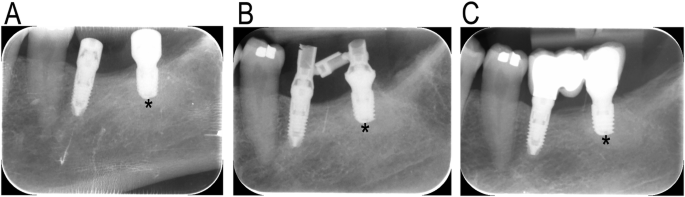

Implant survival was defined as the presence of the dental implant in the patient mouth after 1 year of insertion. Changes in marginal bone level were defined as the changes in the distance between the implant platform and the most coronal contact point at the implant-bone interface in the period between implant loading and 1 year later. For that, periapical radiographs were obtained with parallel technique and using Rinn XPC-ORA radiographic positioner (Dentsply Sirona, Charlotte, NC, USA). The radiographs were assessed in DIGORA® for Windows software (version 2.9.113.490, Soredex, Milwaukee, WI, USA) and were calibrated by the known implant length. The measurements were performed at the mesial and distal aspects of the dental implant. Prosthetic complications were assessed by the frequency of occurrence of technical complications (porcelain fracture, screw loosening, screw fracture, and prosthesis fracture) during the follow-up.

The implants were placed according to standard clinical practice; that is, shorter implants were used when the available bone height precluded the placement of longer implants. All test implants had a length of 5.5 mm. In the control group, 32 implants were 6.5 mm long and 19 were 7.5 mm long. The diameters of the test implants were significantly larger than those of the control implants (Chi-squared test, p < 0.001). The implants in the control group had diameters ranging from 3.0 to 4.25 mm, while those in the test group ranged from 3.0 to 4.7 mm (Fig. 2).

Table 1 shows date relevant to implant placement. The insertion torque had not differed significantly between the study groups (Wilcoxon test, p = 0.671). The median values were 40 and 45 N.cm for the control and test groups, respectively. The bone density significantly differed between the two groups (paired Student’s t test, p = 0.02), being denser in the control group (mean: 694.1 units) than the test group (mean: 624.5 units). However, the distribution of the bone type between the study groups was not statistically different (Chi square test, p = 0.221). All the bone types in the control groups were between bone type I and type III, whereas bone type IV was only present in the test group. As both implant types supported the same prosthesis, the implant loading was identical between the study groups. Delayed loading was performed in 14 of the 18 implants in the maxilla and in 18 of the 66 implants in the mandible.

None of the dental implants failed during the observation period. Table 2 summarizes the data on follow-up times and marginal bone levels around the dental implants. The follow-up duration did not differ significantly between the study groups (Wilcoxon test, p = 0.884). However, the marginal bone level differed significantly between the groups at both the time of loading and at the final radiographic evaluation.

At the mesial side, the control and test implants were subcrestally located, with the implant platforms located 0.7 mm and 1.1 mm below the marginal bone level, respectively (Wilcoxon test, p = 0.003). At the last radiograph, the implant platforms were located 1.0 mm and 0.4 mm below the marginal bone level in the control and test groups, respectively (Wilcoxon test, p = 0.02).

On the distal side, the implant platforms were located 0.3 mm and 0.8 mm subcrestally in the control and test groups, respectively (paired Student’s t-test, p < 0.0001). At the last radiograph, these distances were 0.0 mm and 0.7 mm, respectively (paired Student’s t-test, p = 0.0000).

Despite these positional differences, the change in marginal bone level over time did not differ significantly between the study groups at either the mesial (Wilcoxon test, p = 0.138) or distal sides (paired Student’s t-test, p = 0.0633) (Fig. 3).